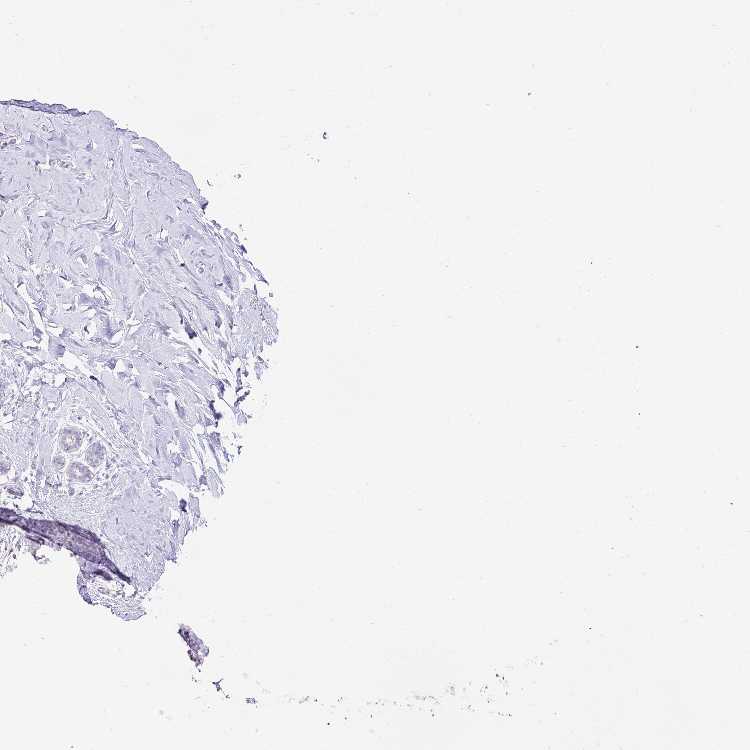

BREAST - Antibody stainingi

Antibody staining in the annotated cell types in the current human tissue is reported as not detected, low, medium, or high, based on conventional immunohistochemistry profiling in selected tissues. This score is based on the combination of the staining intensity and fraction of stained cells.

Each image is clickable and will lead to virtual microscopy that enables deeper exploration of all samples and also displays staining intensity scores, fraction scores and subcellular localization as well as patient and tissue information for each sample.

Antibody HPA055783

Adipocytes Not detected

Glandular cells Not detected

Myoepithelial cells Not detected